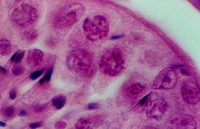

Stratified Columnar epithelium is rare. One place you can find it is in the largest ducts of salivary glands (parotid, submandibular, etc). The basal layer of cells are cuboidal cells and the layer nearest the apical surface includes columnar cells. The large droplets are mucus, in Goblet cells. This also illustrates the fact that epithelia are classified according to the cells nearest the lumen, in this case columnar.